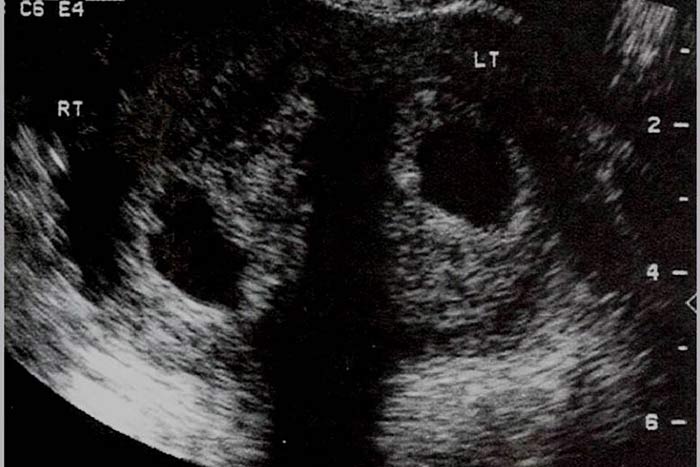

رویت ناچ بیشتر از یک سانتی متر در فوندوس رحم مطرح کننده رحم دو شاخ می باشد.هر دو شاخ در ظاهر و اندازه قرینه هستند و ارتباط کامل بین هر دو شاخ وجود دارد.در هیستروسونوگرافی دو آندومتر دیده می شود. (8،7)

در هیستروسونوگرافی فوندوس رحم کاملا صاف و یا با کمی تحدب دیده می شود ممکن است تقعر کمتر از 1 سانتی متر وجود داشته باشدو در رحم سپتوم دار دو آندومتر دیده می شود. در مواردیکه سپتوم کامل است سپتوم تا ext. os ادامه می یابد و ممکن است در هیستروسکوپی نمایی شبیه رحم دو شاخ داشته باشد.